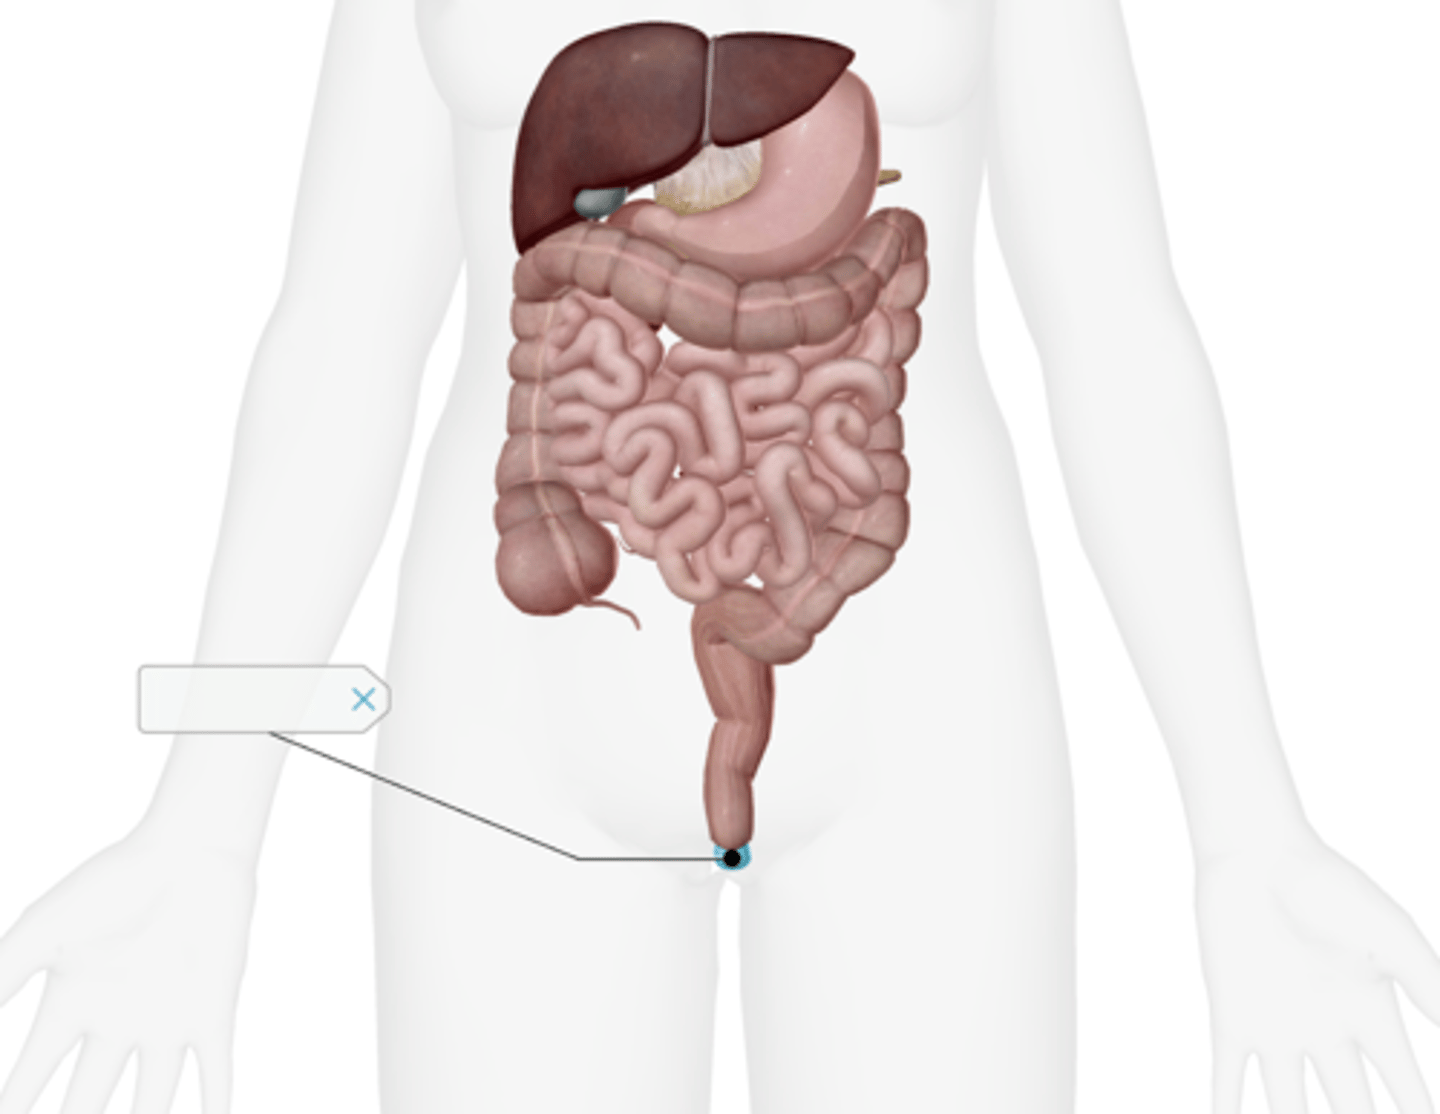

Appendix